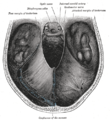

The fornix and corpus callosum from below.